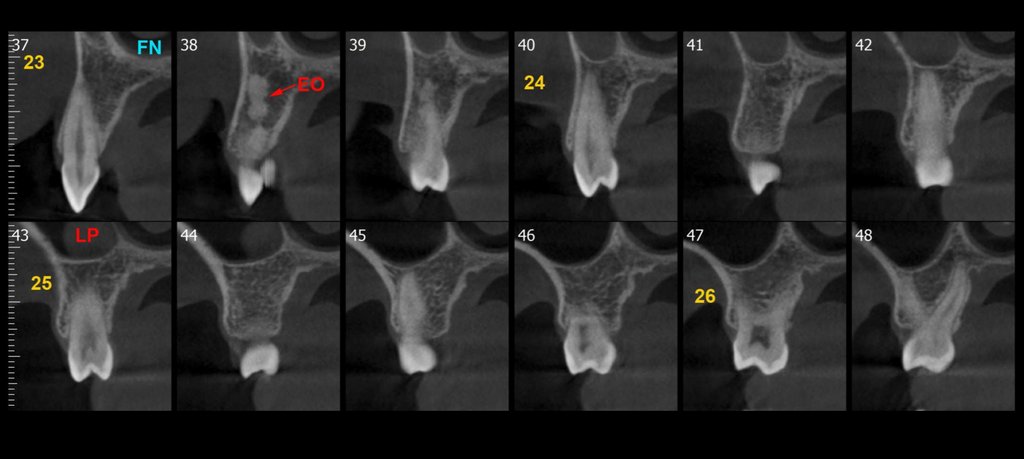

Crown lengthening 11 - 8mm

10,5mm

9,5mm

8,7mm

10,2mm

8,3mm

0,5mm

1mm